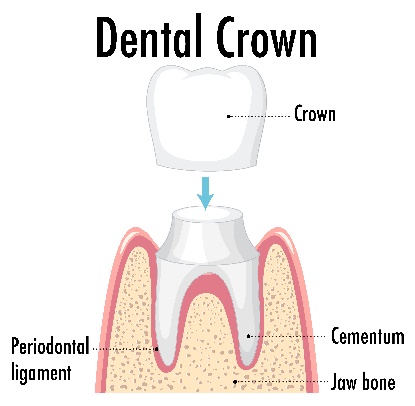

Dental crowns are caps of restorative materials that cover the circumference of the tooth crown (the visible part of the tooth in the oral cavity) to restore or strengthen it.

A specific amount of tooth structure must be removed to create space for the crown to be properly seated. Failing to achieve adequate room for crown construction can result in bulging crowns, which are deemed failures in terms of aesthetics and hygiene.

The initial step for crown fabrication is tooth preparation. If the tooth is still vital, local anesthesia will be administered to numb the tooth, and then the tooth structure is removed to create room for the dental crown.

The second visit is scheduled after the dental labs finish your permanent restoration. The temporary crown will be removed, and the tooth will be cleaned of any residual temporary cement.

The permanent crown is placed and checked for marginal fit, bite, and shade. If all aspects are satisfactory, a durable cement will be applied to secure your new crown.